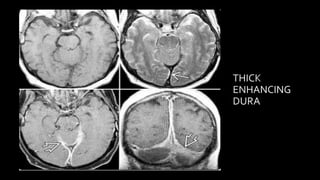

MR IMAGING FEATURES

Acute DST

(Fat sinus)

T2* "blooms "empty delta"

Subacute DST

Chronic DST

"squiggly" parenchymal enhancement

, thick enhancing dura

Thrombus in SSS

FILLIN

G

DEFEC

T IN

SSS

FILLING DEFECT IN SSS

FILLING DEFECT IN LEFT TS

• #138 Subacute thrombus appears hyper on all sequences….. Clot signal in chronic dst is variable and depends on organization of clot….. LONG STANDING DST MAY DEVELOP SIGNIFICANT COLLATERAL FORMATION THROUGHT MEDULLARY VEINS WHICH IS SEEN AS SQIGGLY PARENCHYMAL

• #139 T2 * SWI shows innumerable prominent tortuous corkscrew squiggly medullary veins throughout both cerebral hemisphers . Venous DSA shows that distal SSS is occluded while proximal and mid seg are patent . Numourous enlarged medullary veins appears to hang in space . This is chronic SSS thrombosis with medullary collateral draingae

• #140 c/o Long standing chronic sss showing thick dural enhancement alonmg tentorium.

• #141 These IS THE axial T2shows absence of normal flow void and hyperintense thrombus in SSS and TOF3d multislab image shows filling defect in SSS